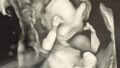

🌿【妊娠18週】大腿骨が短い…

妊娠18週で「大腿骨が短い(−3.2SD)」と言われ不安でいっぱいに。胎児スクリーニングの結果、染色体異常の可能性、羊水検査の選択、もう一人の先生の診察で分かった「脳に異常なし」という安心材料まで、同じ経験をしている妊婦さんに向けて正直に記録しました。